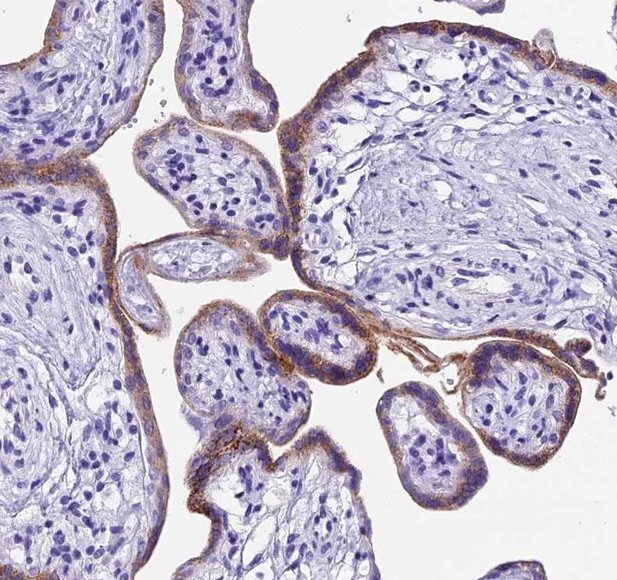

PDL1 Expression by Trophoblastic cells protects from maternal rejection

Human trophoblastic cells display many of the features of malignant cells such as cellular growth and their ability to invade normal tissue including blood vessels and are apparently not eradicated by the host immune system. These trophoblastic cells are genetically significantly different from the mother and should initiate a maternal immune rejection. This is however suppressed thank to the PD1-PDL1 interaction